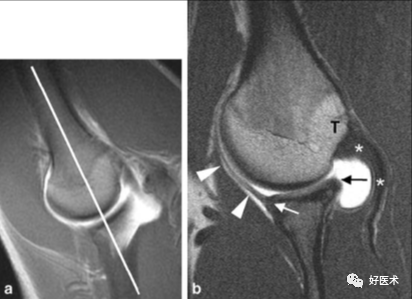

1.Bankart lesion

盂肱下韧带和前盂唇(前下盂唇韧带复合体)从关节盂边缘撕脱,伴肩胛骨骨膜的撕裂。首次损伤后不恰当愈合可导致反复肩关节不稳。

2.Bony Bankart lesion

前下盂唇韧带复合体从关节盂边缘撕脱,伴继发于前关节脱位的肩胛盂骨性骨折。